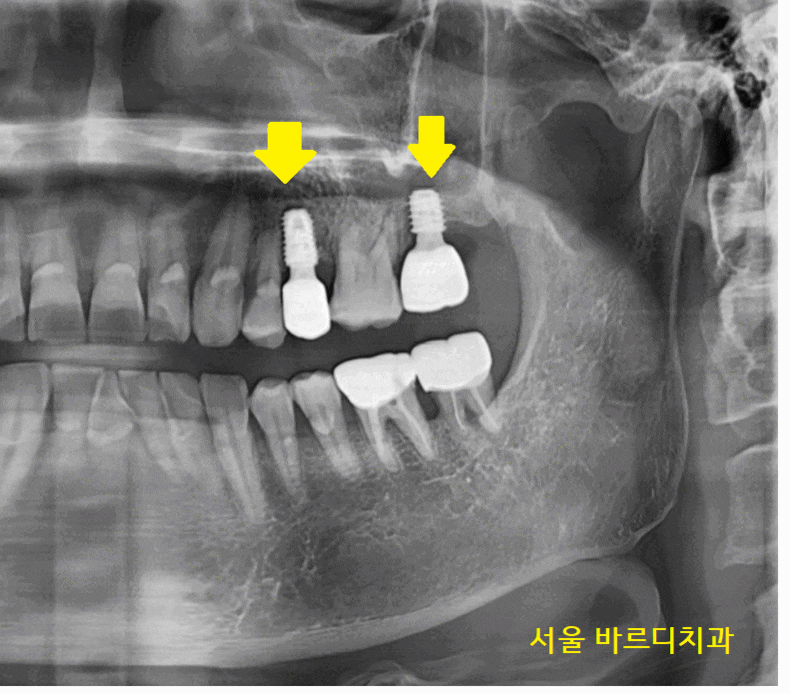

23.12.29

사진을 보시더라도

옆에 치아보다

임플란트 길이가 짧은 게 보이시죠?

시간이 흘러 임플란트와 내 뼈가 잘 붙어서

보철을 만들어드렸습니다.